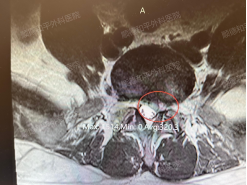

患者入院后,经过专业的问诊和摄片检查,综合判定患者可以实施“微创椎间孔镜髓核摘除术”摘除突出的椎间盘。微创椎间孔镜髓核摘除术——类似在创口插入一只铅笔大小的管子进去实施摘除处理,具有精准摘除、手术时间短、创伤小(创口仅1cm左右)、疼痛小、恢复快速等优势。

能否实施微创术取决于:患者腰椎骨骼没有钙化、年龄、工作性质、症状、个人意愿等方面综合考虑。术式:经皮椎间孔镜下L5-S1椎间盘骨墙核摘除术。